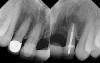

The chief complaint of a 48-year-old woman who presented to her restorative dentist was, “I don’t like the way my implant looks” (Figure 1). This implant had been placed by a previous periodontist and restorative dentist. The patient is now seeking a second opinion. In evaluating this case upon referral to the periodontist, a reddened appearance of the gingival and mucosal tissue encompassing almost the entire facial aspect could be observed. In addition, the radiographs demonstrated a 5-mm diameter implant in place with a deciduous cuspid in the place of No. 11. Deep probing depths were noted around the facial aspect of the implant, and threads could be detected under the tissue.

In evaluating the options, it was decided that the implant placed was too large and that the deciduous cuspid site could be used for a single implant as an abutment for a cantilevered pontic to restore the missing lateral incisor in a more esthetic manner. The goal the treatment was to augment the lateral incisor site in order to bring the facial tissue level more coronal (Figure 2 through Figure 11).